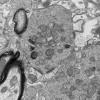

Neuroaxonal dystrophy (3)